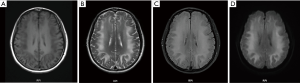

We evaluated her cognitive function with a series of tasks (Tables 1,2), and performed a physical examination, a mental examination, a cranial MRI, and a cerebrospinal fluid (CSF) examination (Tables 3,4). Examinations of her physical health and nervous system indicated the patient’s vital signs were stable. But for slight hyperreflexia of the tendons, her results were normal. In the mental examination, the patient could only answer the doctor’s questions using one or two simple words. For example, when we asked the patient why she came to hospital, she said “cold”. When we asked questions like “how are you feeling now” or “what’s wrong with you”, she was silent. When we asked her what day it was, the patient said, “I don’t know”. The patient’s mental examination indicated she was passive, emotionally apathetic, exhibited slow thinking speed, and had poor thought content. As she showed no psychotic symptoms, such as hallucinations or delusions, and there were no other obvious symptoms, such as decreased interest or insufficient energy, her impairment had gone unnoticed and progressed rapidly. After consulting with the patient and reviewing her medical history, we excluded depressive disorders, schizophrenia, and other mental disorders. Her cranial MRI, however, indicated white matter signal abnormalities (Figure 1).

The patient’s MRI showed extensive white matter signal abnormalities, particularly in the frontal lobe, temporal lobe, basal ganglia, before treatment. This indicated more extensive injuries to these regions (Figure 3). Studies have shown that the frontal lobe, the anterior region of the cerebral hemispheres, controls movement, language, intelligence, emotional regulation, et cetera (22). The temporal lobe, located beneath the lateral fissure of each cerebral hemisphere is involved with emotion, auditory processing, remembering visuospatial information, et cetera (22,23). The parietal lobe, located at the posterior top of the cerebral hemispheres, controls sensory skills and is important in reading, et cetera (24). The functions of these brain regions are consistent with the cognitive dysfunction that the patient exhibited. Compared with her pre-treatment MRI, an MRI taken after one month of treatment showed that the white matter signal abnormalities in these regions had reduced. The size of the areas that showed abnormalities had also decreased. These changes aligned with assessments of the patient’s symptoms and cognitive function, demonstrating that her treatment was effective.